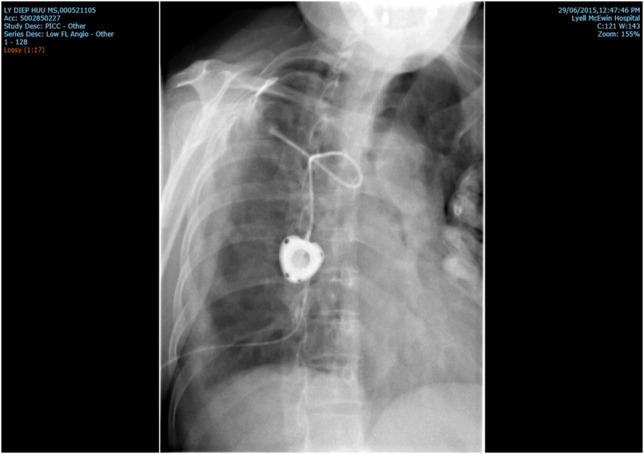

Anthracycline extravasation is a feared complication of intravenous (i.v.) chemotherapy due to the tissue toxicity of this group of drugs. We describe a 54-year-old woman with history of stage IIIa breast cancer, receiving adjuvant chemotherapy consisting of doxorubicin and cyclophosphamide. The chemotherapy was administered through a Poweport device, the position of which was confirmed with fluoroscopy and function confirmed by flushing the line. Urgent intervention was required as patient was symptomatic and experienced severe right-sided pleuritic chest pain. Radiology also confirmed the extravasation of doxorubicin into the pleural space. Surgical washout of the pleural space and 3 days therapy with i.v. dexrazoxane were carried out to prevent tissue damage and long-term sequelae. Use of dexrazoxane should always be considered following intra-pleural extravasation because of its potential efficacy and reasonable tolerability. However, the best approach to extravasation injury is prevention by systematic implementation of careful, standardized, evidence-based administration techniques.

蒽环类药物外渗是静脉化疗令人担忧的并发症,因为这类药物具有组织毒性。我们描述了一名54岁患有IIIa期乳腺癌的女性,她正在接受由多柔比星和环磷酰胺组成的辅助化疗。化疗通过Powerport装置给药,其位置经荧光透视确认,管路功能通过冲洗确认。由于患者出现症状并经历严重的右侧胸膜炎性胸痛,需要紧急干预。放射学检查也证实多柔比星已渗入胸腔。对胸腔进行手术冲洗,并静脉注射右丙亚胺进行3天治疗,以防止组织损伤和长期后遗症。由于右丙亚胺具有潜在疗效和合理的耐受性,胸腔内药物外渗后应始终考虑使用。然而,预防外渗损伤的最佳方法是系统地实施谨慎、标准化、基于证据的给药技术。